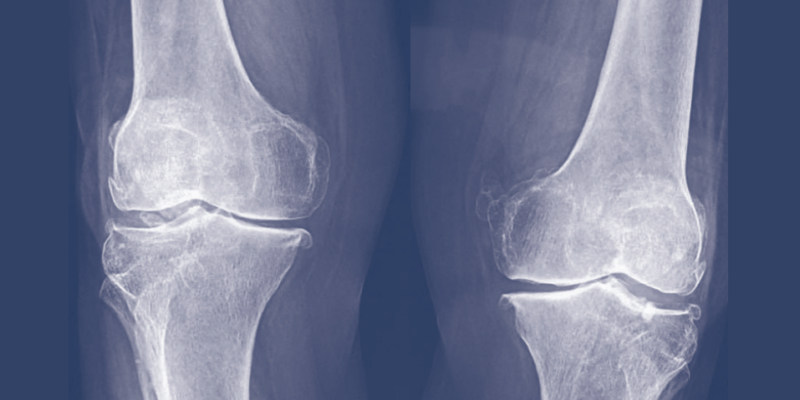

In questo incontro, saranno illustrate le possibili soluzioni per problemi comuni all’anziano come l’osteoporosi e l’artrosi. Saranno forniti al medico delle indicazioni precise in base alla Evidence Based Medicine.